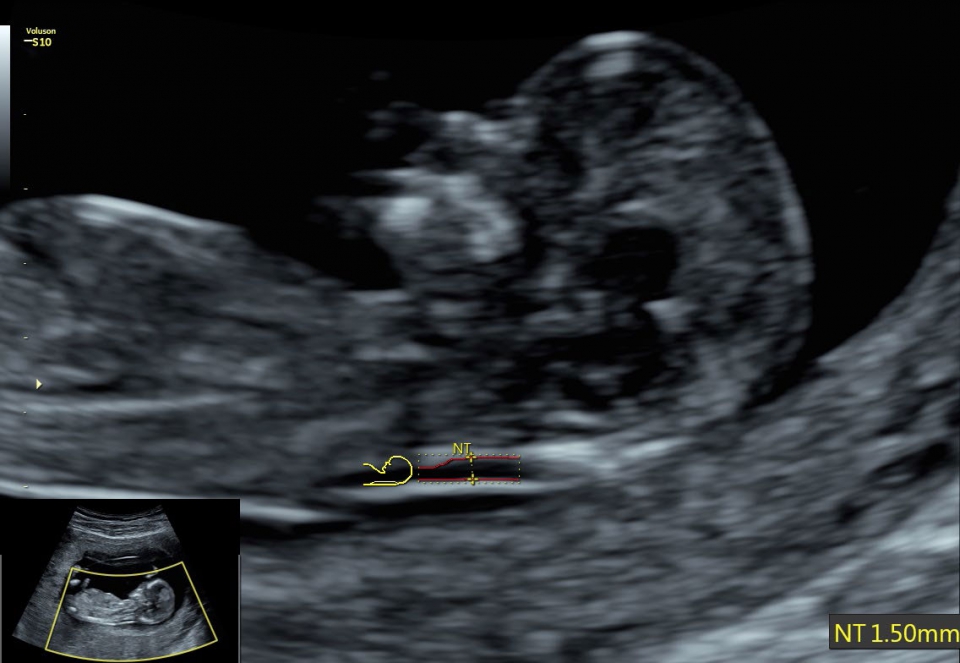

• SonoBiometry (Полуавтоматическая биометрия): Эта технология позволяет проводить измерения биометрических параметров плода, таких как бипариетальный размер, окружность головы, окружность живота, длина бедра и длина плеча. Она упрощает процесс получения точных и надежных измерений.

• SonoNT (Оценка воротникового пространства) и SonoIT (Оценка внутричерепного пространства): Эти технологии позволяют проводить полуавтоматическую оценку толщины воротникового пространства и размеров IV желудочка головного мозга плода в I триместре беременности. Они обеспечивают более точную оценку этих параметров с минимальными усилиями.

• Автоматический расчет толщины воротникового пространства SonoNT и размера четвертого желудочка SonoIT

• SonoBiometry (автоматическое измерение BPD, AC, HC, HL, FL)